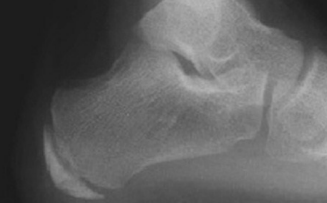

What is this? What foot type is this visible in? | Sinus tarsi/bullet hole sign. Pes cavo-varus |

What is this? What foot type is this visible in? | Double talar dome sign. Pes cavo-varus |